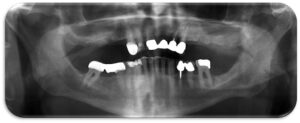

- Προσθετικη επι εμφυτευματων